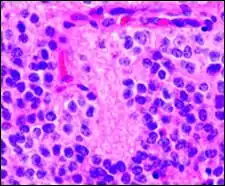

Micrograph of Homer Wright pseudorosettes

A Homer Wright pseudorosette is a type of pseudorosette in which differentiated tumor cells surround the neuropil.[15] Examples of tumors containing these are neuroblastoma, medulloblastoma, pinealoblastoma, and primitive neuroectodermal tumors of bone. Homer Wright rosettes are considered "pseudo" in the sense that they are not true rosettes. True rosettes are Flexner–Wintersteiner rosette, which contain an empty lumen. Homer Wright rosettes contain abundant fibrillary material. They are named for James Homer Wright.